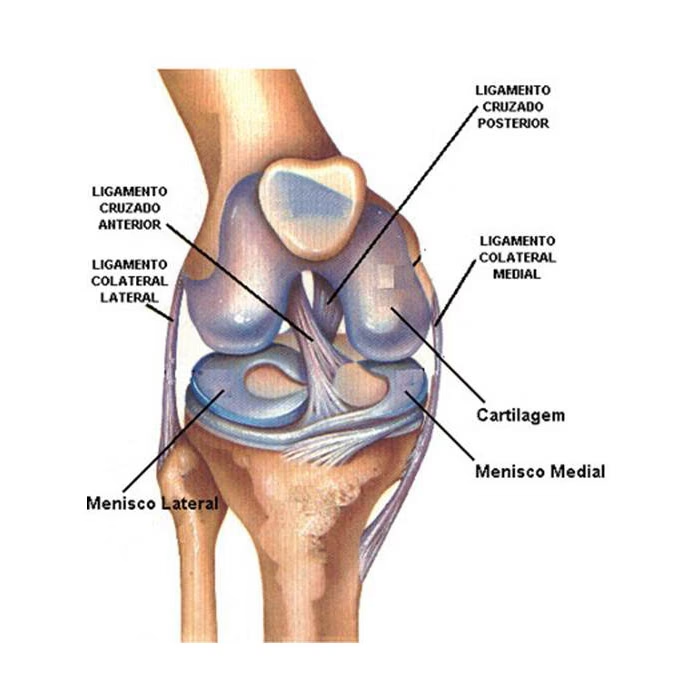

Los ligamentos de la rodilla (cruzado anterior, cruzado posterior, colateral medial, colateral lateral) son cruciales para la estabilidad. Las lesiones del ligamento cruzado anterior (LCA) son particularmente comunes en deportes que implican giros, saltos y cambios rápidos de dirección. La reconstrucción del LCA es una de las cirugías deportivas más frecuentes. En este procedimiento, el ligamento dañado se reemplaza con un injerto de tejido, que puede ser autoinjerto (del propio paciente, como tendón rotuliano o isquiotibiales) o aloinjerto (de un donante). La cirugía se realiza generalmente por artroscopia, minimizando la invasión y el tiempo de recuperación inicial, aunque la rehabilitación completa puede llevar varios meses.

Los meniscos son dos estructuras de cartílago en forma de C que actúan como amortiguadores y estabilizadores de la rodilla. Los desgarros meniscales son lesiones muy comunes, especialmente en deportes o con el envejecimiento. El tratamiento de estas lesiones se realiza con frecuencia mediante artroscopia, una técnica mínimamente invasiva que utiliza una pequeña cámara y herramientas finas introducidas a través de pequeñas incisiones. Las opciones quirúrgicas incluyen: